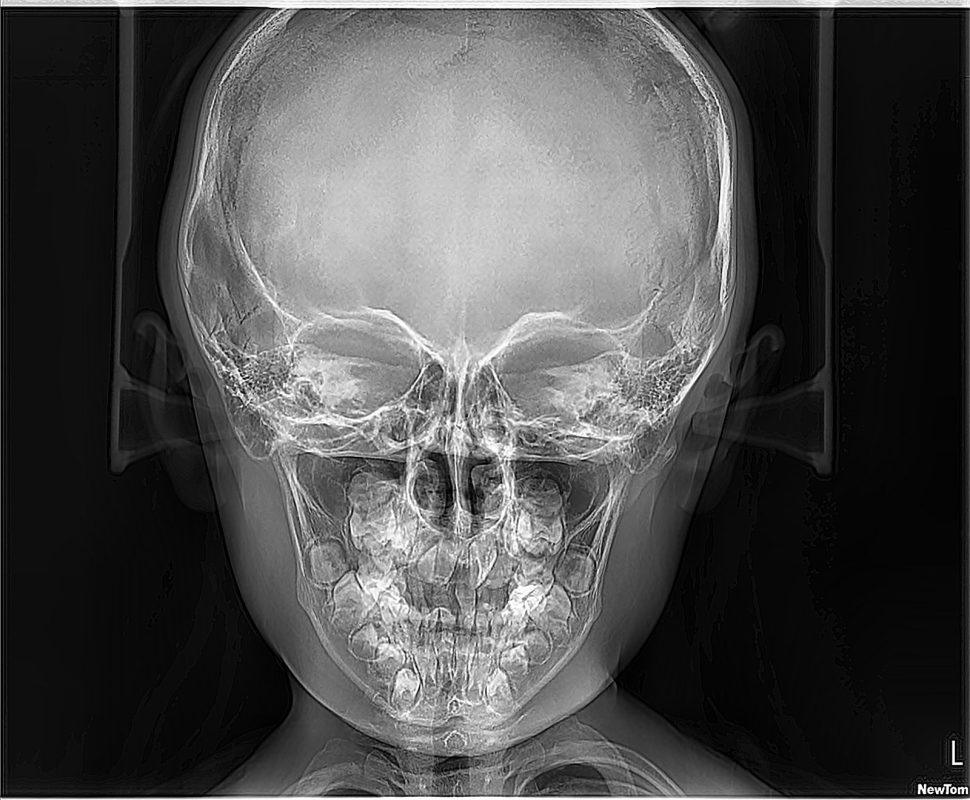

RX SENOS PARANASALES

La radiografía de senos paranasales es una técnica de imagen que se utiliza para examinar las cavidades llenas de aire en los huesos que rodean la nariz, conocidas como senos paranasales. Incluyen los senos maxilares, etmoidales, esfenoidales y frontales. Puede ser realizada para diversos propósitos, como:

CADWELL, CAVUM, WATERS